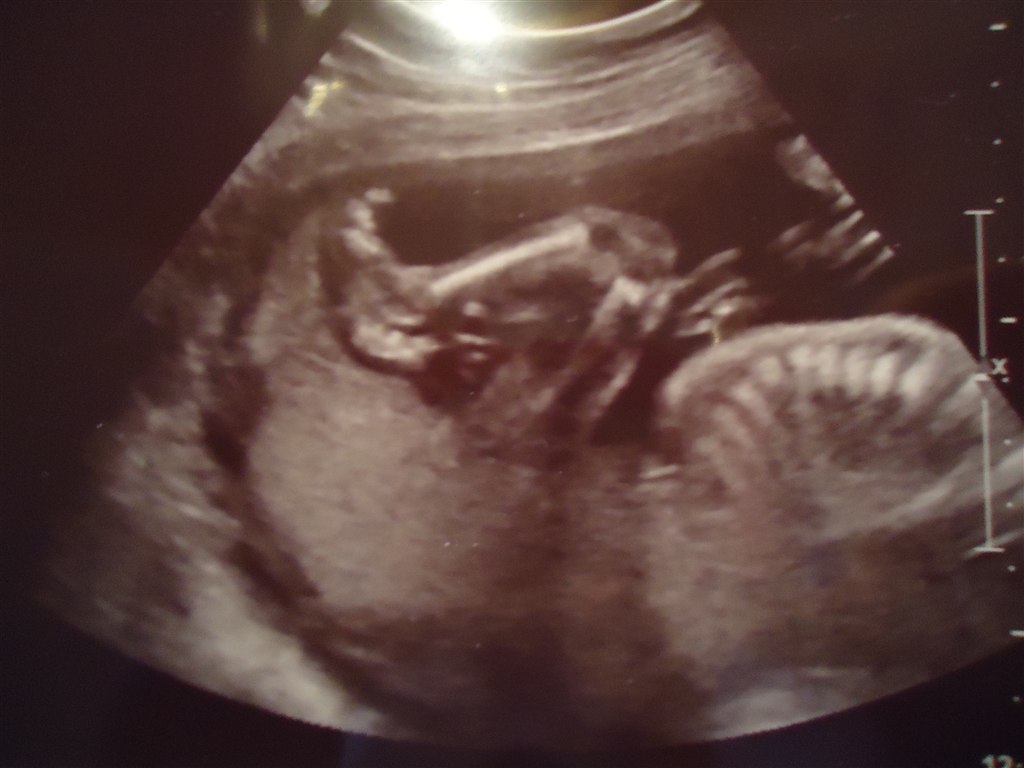

og så var vi til MD-scanning i torsdags, og hun var helt perfekt vores lille pige, 20 cm og 367 gram